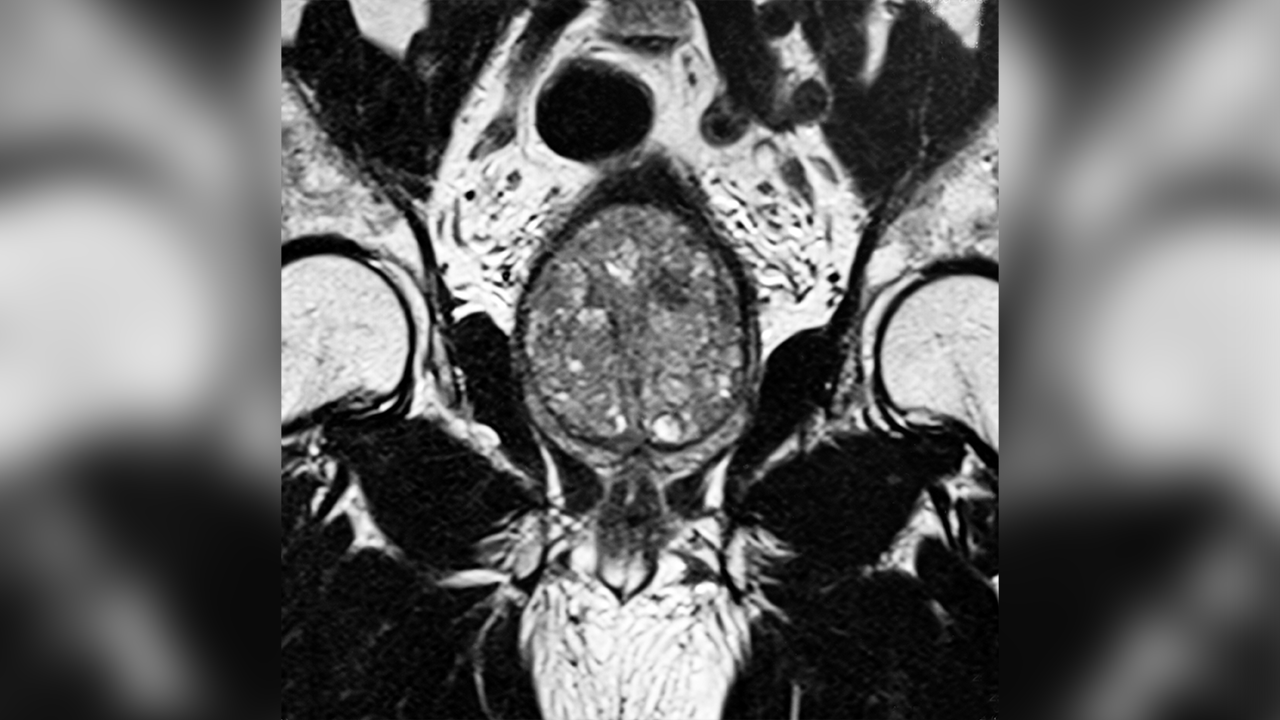

Mount Sinai is adopting new approaches to diagnosis and treatment of benign prostatic hyperplasia (BPH) and engaging patients through innovative disease awareness and management applications.